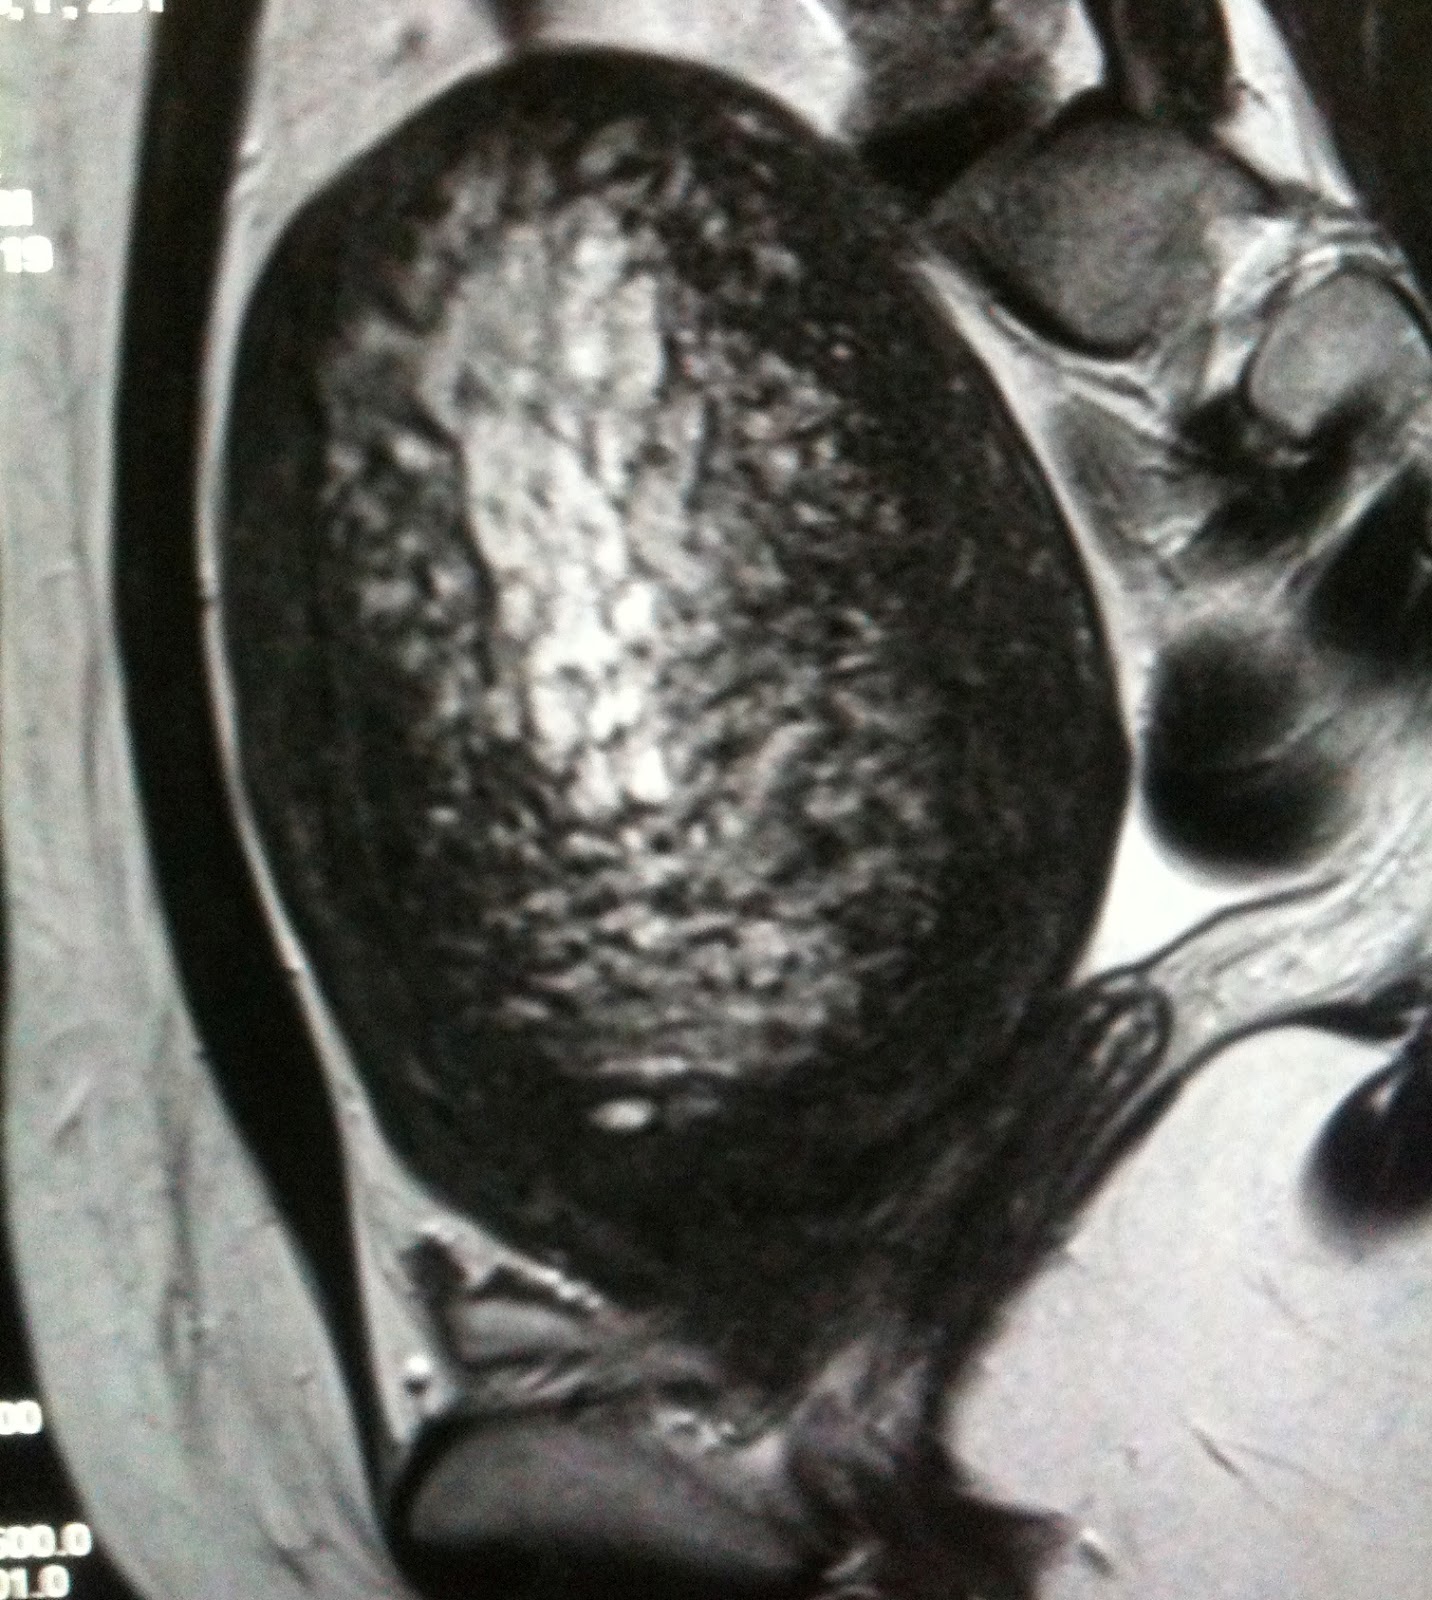

From sapiba.ir

سرطان اندومتر (Endometrial Cancer) sapiba Thickened Endometrium Radiology The appearance, as well as. Endometrial pathology most often manifests as either focal or diffuse endometrial thickening, and patients frequently present with abnormal vaginal. Endometrial hyperplasia is a more common cause of abnormal thickening of the endometrium on ultrasound before menopause. In a woman with postmenopausal bleeding and a thick endometrium, a sonohysterogram can determine whether the endometrium is diffusely.. Thickened Endometrium Radiology.